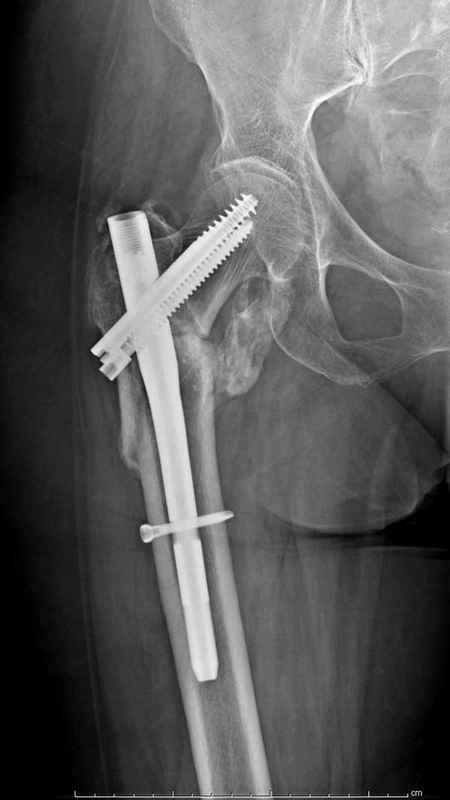

Здесь 83 года, травма в результате падения

Из фиксаторов, мы бы применили цефаломедуллярные, потому что они "по закону моментов" из-за короткого рычага от центра головки к диафизу и по принципу "головка диафиз" механически лучше выдерживают нагрузки, чем пластины.

судя по картинкам с ЭОПа явно использовались приемы непрямой репозиции под его контролем, а так же интраоперационный ЭОП-контроль положения винтов, без такого контроля операция может ухудшить ситуацию (опять же учтите сроки) т.к. результат буде зависеть в большей степени от искусства хирурга, а не от технологии